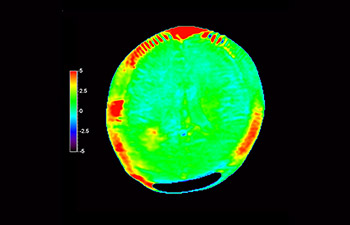

Glioblastoma recurrence

Brain imaging for glioblastoma recurrence

with 3D APT